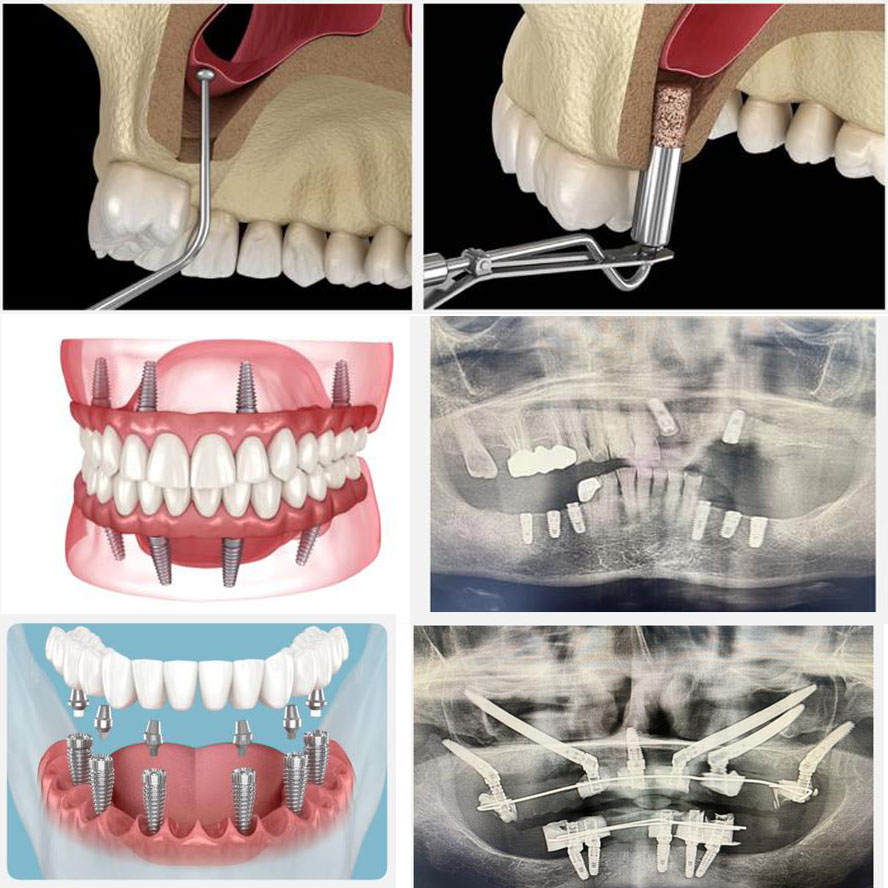

At Goel Dental, Dr. Shikha Goel and her team bring together advanced implant technology and years of expertise to replace missing teeth with results that look, feel, and function like natural teeth.

Don’t let gaps hold you back — regain your bite, confidence, and smile with dental implants designed to last a lifetime.